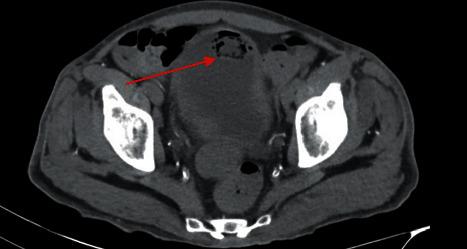

Fungemia due to obstructive urinary tract fungal ball is exceedingly rare. These patients often have multiple predisposing conditions, including diabetes or antimicrobial exposure. While candiduria can be relatively common in this population, urinary tract fungal balls are a rare entity. Hospitalists should be aware of this rare complication in patients presenting with funguria. . We present a case of a 44-year-old male with type II diabetes, chronic hepatitis C secondary to injection drug use, and chronic kidney disease who developed a urinary tract fungal ball leading to fungemia and subsequent bilateral chorioretinitis, additionally complicated by emphysematous cystitis and pyelonephritis. Additional invasive treatment options beyond typical antifungals are often required in the case of urinary tract fungal ball, and in this case, bilateral nephrostomy tubes and micafungin were employed. Hospital course was complicated by fungemia with subsequent bilateral fungal chorioretinitis on dilated fundus exam. This was effectively treated with cyclogyl and prednisolone drops along with bilateral voriconazole injections. Follow-up imaging and cultures showed resolution of fungemia, urinary tract masses, and chorioretinal infiltrates; however, recurrent polymicrobial UTIs continue to be an issue for this patient.

梗阻性尿路真菌球引起的真菌血症极为罕见。这些患者通常有多种易感因素,包括糖尿病或抗菌药物暴露。虽然念珠菌尿在该人群中可能相对常见,但尿路真菌球是一种罕见的病症。住院医生应意识到在出现真菌尿的患者中存在这种罕见并发症。我们报告一例44岁男性患者,患有II型糖尿病、因注射吸毒继发慢性丙型肝炎和慢性肾脏病,他发生了尿路真菌球,导致真菌血症及随后的双侧脉络膜视网膜炎,此外还并发气肿性膀胱炎和肾盂肾炎。对于尿路真菌球病例,通常需要除典型抗真菌药物之外的其他侵入性治疗选择,在本病例中,采用了双侧肾造瘘管和米卡芬净。住院期间病情因真菌血症而复杂化,散瞳眼底检查发现随后出现双侧真菌性脉络膜视网膜炎。使用环喷托酯和泼尼松龙滴眼液以及双侧伏立康唑注射有效地治疗了该病。随访影像学检查和培养显示真菌血症、尿路肿块和脉络膜视网膜浸润消退;然而,复发性多种微生物尿路感染仍是该患者的一个问题。